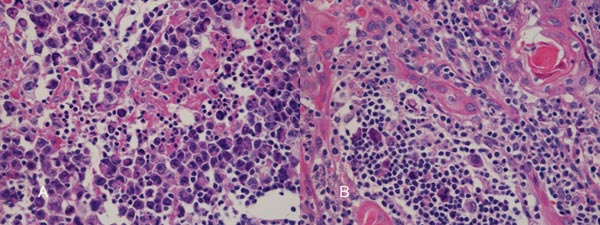

胸腺癌(悪性胸腺腫、浸潤性胸腺腫)

胸腺癌(悪性胸腺腫、浸潤性胸腺腫)は非常に稀で、標準的な治療が存在しません。組織型も、扁平上皮癌・未分化癌・小細胞癌と多様です。甲状腺機能亢進症/バセドウ病に合併した

縦隔の悪性リンパ腫

胸腺腫/胸腺癌(悪性胸腺腫)は、少なからずリンパ組織の増殖を認めるため、sIL2-R (可溶性インターロイキン2受容体) 高値となり、縦隔の悪性リンパ腫と鑑別を要します。また、胸腺に発生する悪性リンパ腫は、胸部外科で開胸生検で鑑別するしかないでしょう。